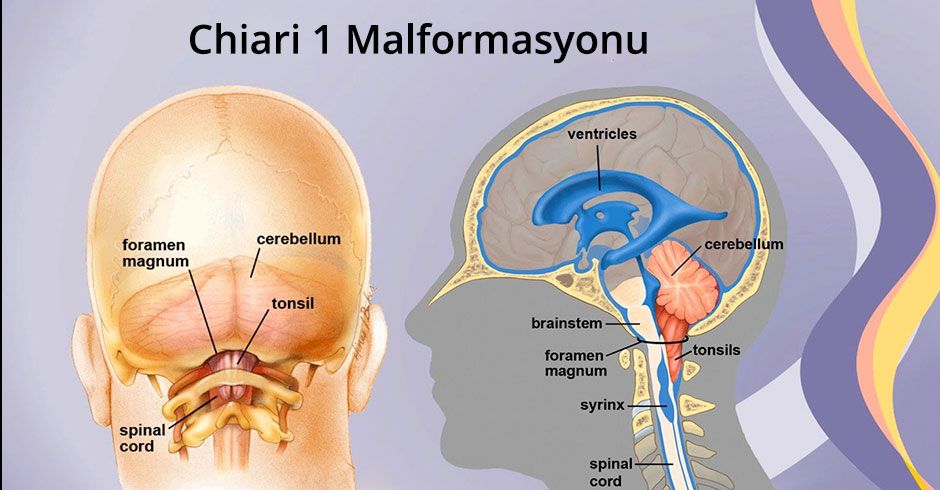

Аномалия Арнольда-Киари: MRI снимки